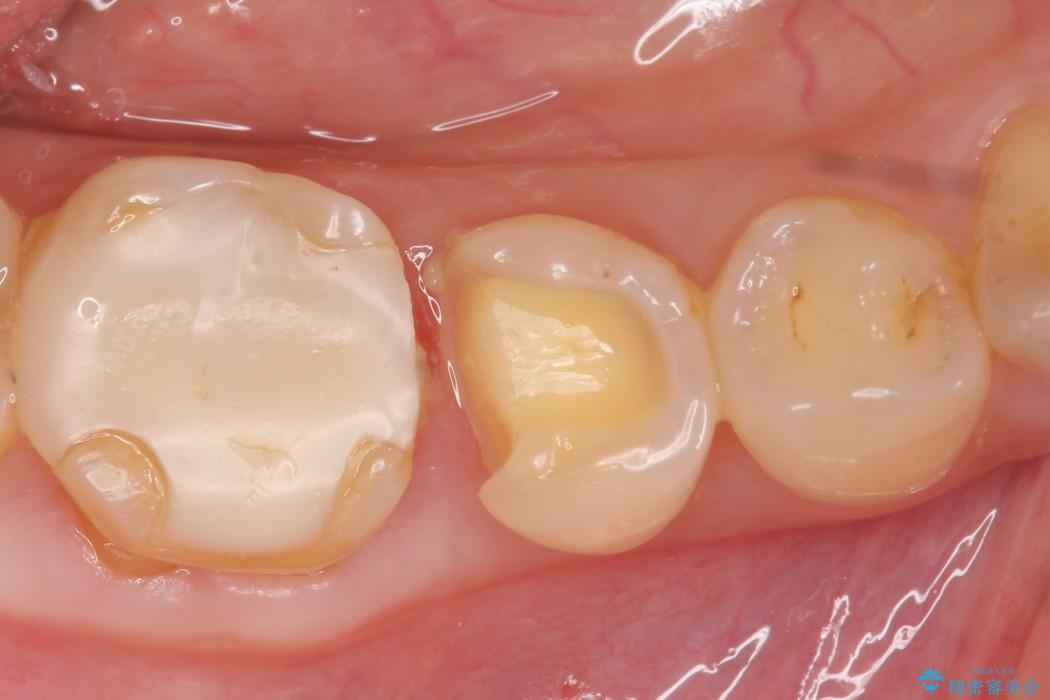

適合不良であるインレーを放置するリスクを患者様へ説明してご納得いただいた上で、オールセラミックインレーで治療を行うこととしました。

そうならないためにも適合の良い剛性にも優れた素材を用いた治療を求められます。特にセラミックが使用されたインレーは見た目が自然なだけでなく適合性、剛性共に高い水準を持つためリスクを減らすことができます。

しかしセラミックは金属に比べて強い衝撃には弱く欠けたり割れてしまう可能性があるため注意が必要です。